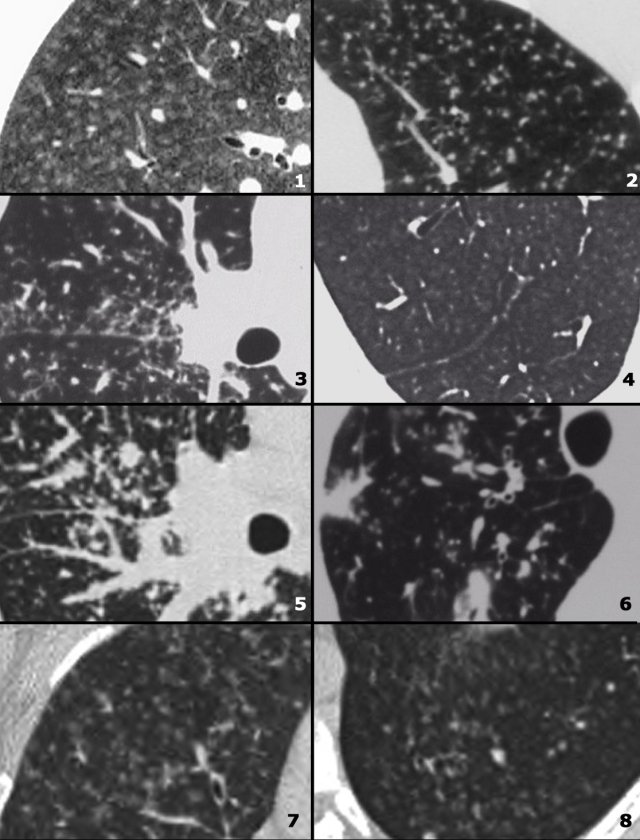

On the left two cases of NSIP.

Note the varying combination of GGO and fibrosis (traction bronchiectasis), but the lack of honeycombing.

In the images on your left you can appreciate again the spectrum of findings seen in NSIP.

All three patients were suffering from connective tissue disease, all cases were biopsy proven.

The first (top left) shows a very subtle GGO.

Note the difference in the density of the air within the bronchus and surrounding lungparenchyma (dark bronchus sign).

The second (top right) is a more obvious example of GGO with a superimposed fine reticular densities as a result of thickening of the intralobular septa.

The last image also shows GGO with a fine reticular pattern.

Notice the lack of honeycombing in all three cases, excluding UIP as diagnosis.